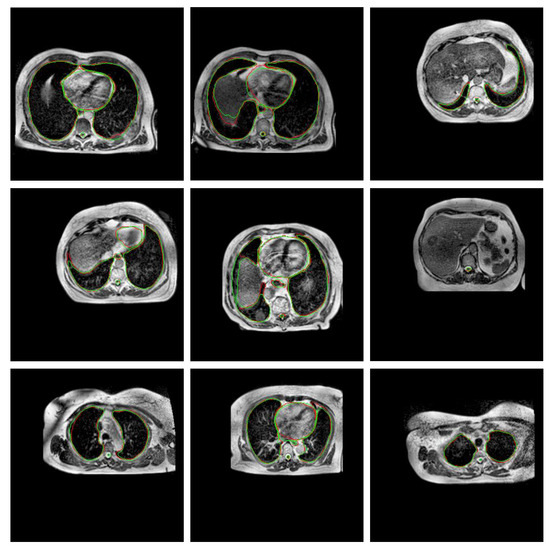

2.2. Preprocessing